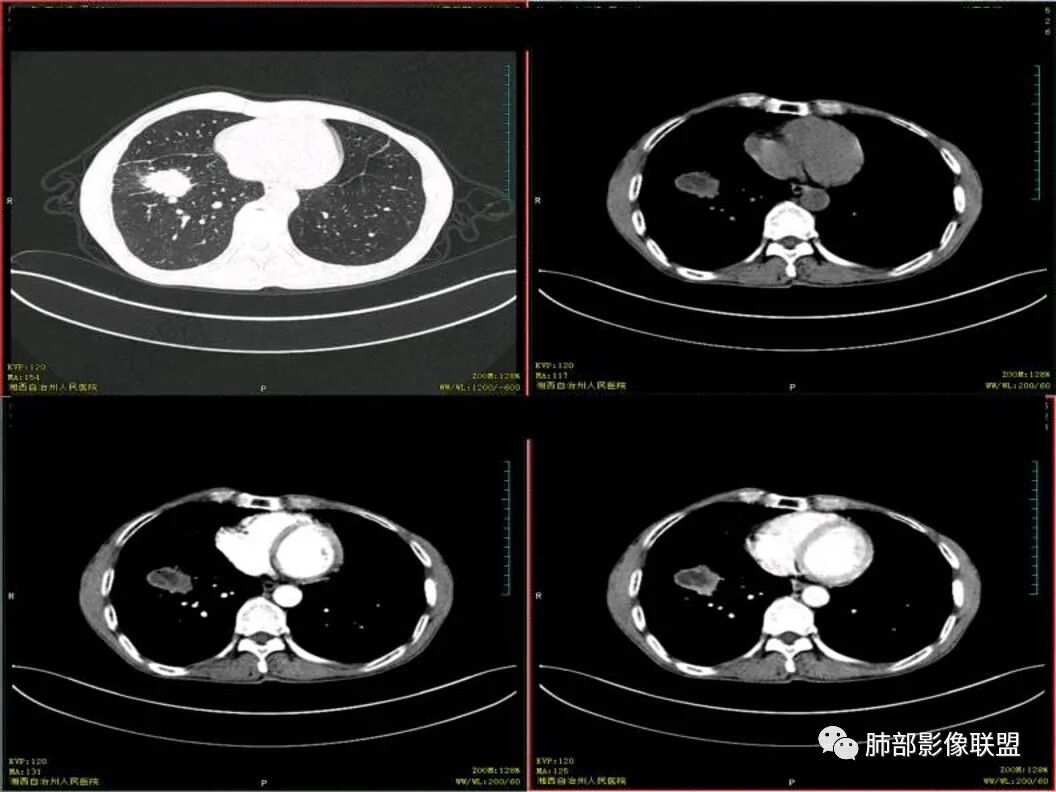

双肺肺气肿伴纤维索条,结节影,以双上肺为主,部分可见支气管扩张,右肺下叶实性肿块,边缘毛糙,病灶较密实,支气管堵塞可能?平扫密度尚可,增强后不均匀强化,叶裂可见多个结节影,纵隔淋巴结肿大,考虑:肺癌伴陈旧性肺结核,肺脓肿伴陈旧性结核

双肺上叶多态,多灶,支持结核。右肺下叶肿块,边缘模糊,毛刺,胸膜牵拉,中央坏死,不均匀强化,似乎有壁结节,斜裂增厚,纵隔淋巴结肿大,二元,结核+鳞。鉴别结核+曲霉。

双上肺多发条索及斑片状,局部支气管扩张,考虑结核。右下肺病灶分叶毛刺,胸膜牵拉,不均匀强化,坏死。纵隔淋巴结肿大,坏死,考虑右下肺肺癌并淋巴结转移,鳞癌可能。

中年男性,双肺多形性病变,双上肺纤维条索影及片状影,右肺下叶团块,有分叶,胸膜牵拉,毛刺,增强示坏死明显,坏死边界较清,也可能是容积效应,周围卫星灶,目测没看到明显支气管堵塞,一元考虑结核,二元考虑结核合并恶性肿瘤(鳞癌?)

临床 中年男性,咳嗽盗汗、老结核史,血沉高、t试验阳性,结核应该存在,cyf高4倍,价值怎么样待验证。影像 :两上肺实变加粗大索条灶,两肺野弥漫粟粒,考虑结核应该问题不大。重点分析右下病灶:隆突下淋巴结肿大,但伴钙化,有边缘强化?淋巴结融合又是恶性征像?右下肺病灶冠状位总体方正,横断位总体三角型,长毛刺、近端也有渗出、坏死彻底、空洞壁光滑锐利,似有边缘强化?看做薄壁空洞?以上符合炎性病灶。   支持恶性的征像 :冠状位的空洞似有壁结节,偏心坏死。   综合 ,右下肺鳞癌(偏心空洞+cfy)+两肺结核。

右下叶前基地段肿块,不规则边缘,周围树丫和长短毛刺,内部小空泡,强化后环形强化,纵膈淋巴结肿大,并有不规则环形强化和钙化,总体考虑感染性病变,结核病。

右下叶肿块鳞癌待除外。